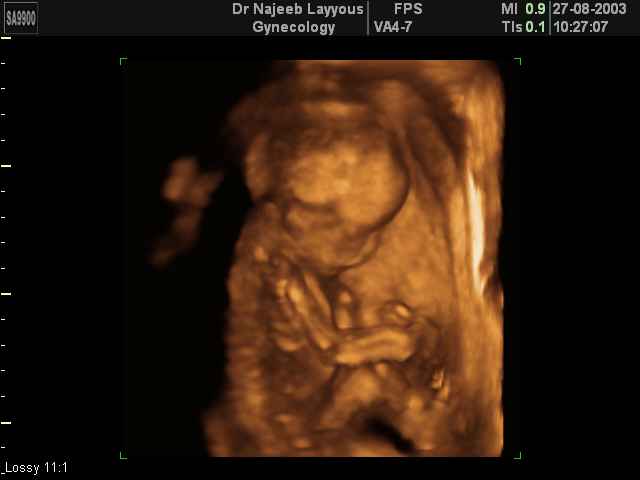

- Fetal Behavior Ultrasound Photos

Ultrasound Photos in 3D showing Fetal Behavior Inside the uterus | Dr N Layyous